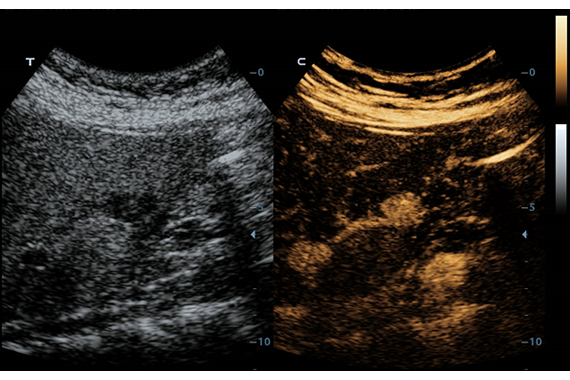

Система ультразвукового исследования Mindray DC-60 EXP X-INSIGHT является новейшей разработкой для проведения комплексных обследований на высшем уровне. Она обеспечивает решение самых сложных задач в таких областях, как кардиология, акушерство и гинекология, сосудистые заболевания, педиатрия и многие другие.

DC-60 EXP X-INSIGHT - это современный стационарный УЗИ-аппарат с функцией сенсорного управления и очищенной гармонической визуализацией, обеспечивающей лучшее контрастное разрешение и технологию 4D-визуализации. Он оснащен 21,5-дюймовым монитором, который может поворачиваться на 180 градусов, что удовлетворяет потребности врачей в качественной ультразвуковой диагностике.

• UWN Contrast Imaging™ - опция для проведения обследования с применением контрастных веществ (поддерживается на датчиках L9-3E и P4-2)

• UWN Contrast Imaging™ QA - пакет для количественного анализа при проведении обследований с применением контрастных веществ (требуется установленная опция UWN Contrast Imaging)